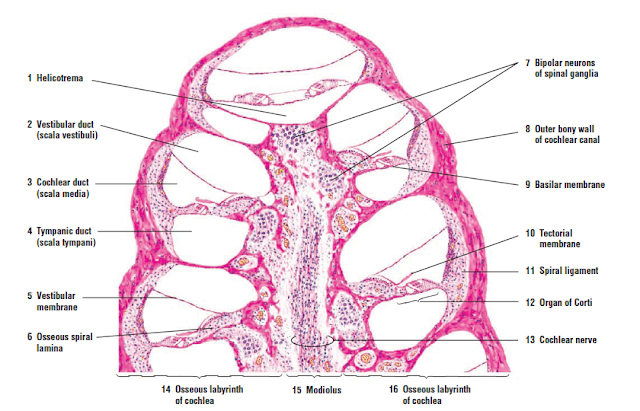

Ducts Cochlea Diagram